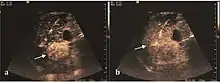

Dysplastic nodules (DN)

These lesions have various patterns (hypo or hyperechoic) with at least 1 cm diameter. They are hepatocytes with dysplastic changes, but without clear histological criteria for malignancy. They are divided into low-grade dysplastic nodules, where cellular atypia are mild and high-grade dysplastic nodules with moderate or severe cellular atypia, but without any established signs of malignancy. Occasionally, well-differentiated HCC foci can be identified in high-grade dysplastic nodules (appearance called "nodule in nodule") . Most authors accept the carcinogenesis process as a progressive transformation of DN from low-grade to high-grade and into HCC. The nodule's vasculature changes progressively, correlated with the degree of malignancy, and it is characterized by decrease until absence of portal venous input and by increase of arterial intratumoral input. Neoformation vessels occur with increasing degree of dysplasia. Arterial neovascularization is enhanced in a chaotic and explosive way, while normal, arterial and portal vasculature continues to decline. High-grade dysplastic nodules are hypovascularized both arterial and portal phases, while early HCC nodules may have similar arterial pattern with the surrounding parenchyma or exacerbated, and portal hypovascularization. In moderate or poorly differentiated HCC (classic HCC) tumor nutrition is performed only by neoformation vessels (abundant), the normal arterial and portal vasculature completely disappearing. This behavior of intratumoral vascularization is typical for HCC and is the key to imaging diagnosis.

B-mode ultrasonography is unable to distinguish between regenerative nodules and borderline lesions such as dysplastic nodules and even early HCC. Doppler examination also has a low sensitivity in differentiating dysplastic nodules from early HCC. Doppler signal may be absent in both regenerative and dysplastic nodules. Some authors indicate the presence of venous type Doppler flow which reflects the portal venous nutrition of the nodule as a characteristic feature of dysplastic nodules and early HCC (Minami & Kudo, 2010). Other authors noticed the presence of an arterial flow with small frequency variations and a normal resistivity index. On CEUS examination both RN and DN may have quite a variable enhancement pattern. Generally, both nodules enhances identically with the surrounding liver parenchyma after UCAs injection. Dysplastic nodules are hypovascular in the arterial phase. In case of highgrade dysplastic nodule sometimes a hypervascularization can be detected, but without associating "wash out" during portal and late CEUS phases. In these cases, biopsy may clarify the diagnosis.